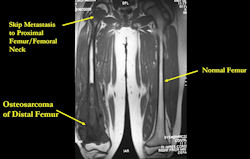

Skip metastases: metastases within the same bone, or across the joint in the adjacent bone, as the primary osteosarcoma

- spread via intraosseous or transarticular venous system within the bone

- rare; may occur without any evidence of pulmonary metastases

- traditionally associated with poor prognosis, although recent reports may suggest otherwise

- detection of skip metastases is important for surgical planning; occasionally, presence of skip metastases may dictate that the entire bone be surgically removed

MRI: Osteosarcoma of distal femur with skip metastasis to proximal femur